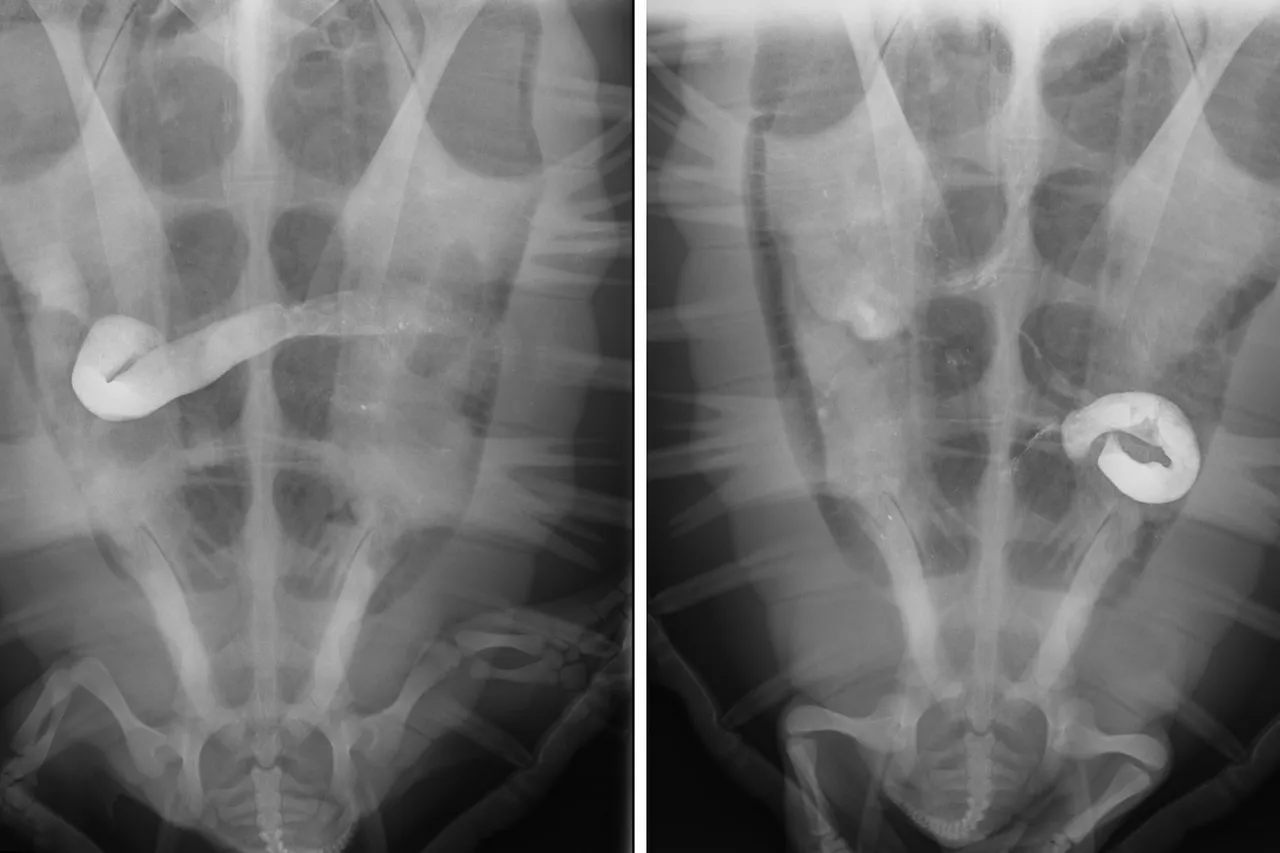

Turtles get X-rayed so we can see their poop

Moms and dads know when their little ones are having tummy trouble - bloating, runny tummies, crying and pointing to an owwie - kids make it easy for parents to know there is a problem. Unfortunately, while sea turtles have the same problems, we don't have any of those clearly visible indications that something is wrong!

Because turtles have very slow metabolisms, they can go weeks or even months without pooping. This makes it difficult to know if a new arrival at the rescue clinic is facing something serious, like gut stasis caused by injuries from ingested plastic, or is just a little stressed, but otherwise fine. Because of their hard shells, there is no easy way to see inside a turtle...

That's where X-rays come in. The Two Oceans Aquarium's veterinary clinic is at the disposal of the turtle team, who can use it to carry out a "contrast study" - a procedure where a turtle is fed a material (barium in our case) that reflects X-rays. This allows the team to see the fluid as it moves through a turtle's gut, and help find any internal injuries - allowing the team to make informed care decisions!